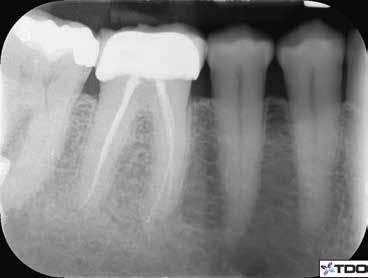

1. a-n. ábrák: Preoperatív CBCT-felvétel a bal alsó 6-os (3.6) fogról. Az axialis (a), coronalis (b) és sagittalis (c) nézeteken a mezialis és distalis gyökerek apicalis harmada körül sugáráteresztő zóna és ép buccalis corticalis csont látható. Egy olyan sablont terveztünk, amely jelezte a csontablak határait az apicalis terület pontos elérése érdekében (d). A mikrosebészeti bevatkozás során a sablont a helyére illesztettük (e), a csontablak határait megjelöltük (f) egy Piezotome CUBE LED kézi-darabba fogott fűrésszel, majd kivágtuk és eltávolítottuk (g és h) az apicalis területhez történő hozzáférés, illetve a mezialis és distalis gyökerek rezekciójának, retrográd preparációjának és retrográd gyökértömésének elvégzése érdekében (i). Végezetül a csontablakot visszaillesztettük és kollagén szivaccsal stabilizáltuk (j). A műtét után közvetlenül készített röntgenfelvétel a 3.6-os fogról (k). A kétéves kontroll során készített CBCT-felvétel: axialis (l), coronalis (m) és sagittalis (n) nézetek.

Egy 63 éves páciens korábban már kezelt bal alsó első nagyőrlőfogából (3.6) eredő mérsékelt fájdalom miatt kereste fel rendelőnket. A kórtörténetében panasza szempontjából releváns információ nem szerepelt. Az elkészült CBCT-felvételen a korábbi kezelések során észre nem vett, jelenleg feltáratlan meziobuccalis csatornát, valamint a mezialis és distalis gyökerek körül kialakult periapicalis elváltozást, és ezt a léziót borító intakt buccalis corticalis csontlemezt láttunk.

A fog revideálását és újbóli gyökértömését két ülésben végeztük el. A régi gyökértömés eltávolítását, valamint mindhárom gyökércsatorna megmunkálását és fertőtlenítését követően kalcium-hidroxid alapú gyógyszeres zárást helyeztünk a gyökércsatornákba. A gyökértömés egy héttel később került behelyezésre. A páciens panaszai két hónap elteltével sem szűntek.

Klinikai vizsgálat során vertikális kopogtatási érzékenységet jelzett. A fog körül mérhető szondázási mélység és a fogmobilitás fiziológiás volt. A CBCT-felvételen nem észleltünk a csontos regeneráció megindulására utaló jeleket (1. a–c. ábrák). A korábban gyökérkezelt, gyökértömött és revideált 3.6-os fog esetében az alábbi diagnózis került felállításra: periodontitis periapicalis symptomatica. A panaszokat okozó fog további ellátása során navigált endodonciai mikrosebészetet kívántunk alkalmazni. Az alsó állcsontról intraorális szkent (TRIOS, 3Shape) készítettünk, és a felszíni topográfiát tartalmazó STL fájlt, valamint a CBCT-felvétel készítése során nyert DICOM fájlokat a Blue Sky Bio szoftver segítségével egyesítettük. A sebészi sablon megtervezésére az így kapott háromdimenziós képet használtuk. A sablon kialakítása során arra törekedtünk, hogy a sablon egyértelműen meghatározza a gyökércsúcsi terület eléréséhez szükséges csontablak határait (1. d. ábra)

A beavatkozás során helyi érzéstelenítésben teljes vastagságú mucoperiostealis lebenyt képeztünk, és a sablon segítségével bejelöltük a preparálandó csontablak határait. Az ablak széleinek megfelelően Piezotome CUBE LED kézi-darabbal (ACTEON) a kortikális teljes vastagságában vágást ejtettünk, majd az így kapott csontlemezt (ablakot) eltávolítottuk (1. e–h. ábra), és ezt követően steril fiziológiás sóoldatba helyeztük. A rezekció elvégzését követően (1. i. ábra) a mezialis csatornákat ultrahangos eszközök segítségével (NSK) retrográd irányból preparáltuk, majd az így kialakított mélyedésbe retrográd gyökértömést készítettünk. A tömés anyagául az EndoSequence BC RRM Fast Set Putty-t (Brasseler) választottuk. A tömés elkészítését követően a csontablakot visszaillesztettük, és a stabilizálása érdekében a vágásoknak megfelelően kialakult résekbe kollagén szivacsokat (Collagen Tape, Zimmer Biomet) helyeztünk (1. j-k. ábra). A lebenyt 6/0-s Prolene varratokkal (Corpaul) rögzítettük.

A kétéves kontroll során elvégzett klinikai és radiológiai vizsgálat (CBCT-felvétel) a periapicalis elváltozások megszűnését és a corticalis csontállomány tünet- és szövődménymentes gyógyulását